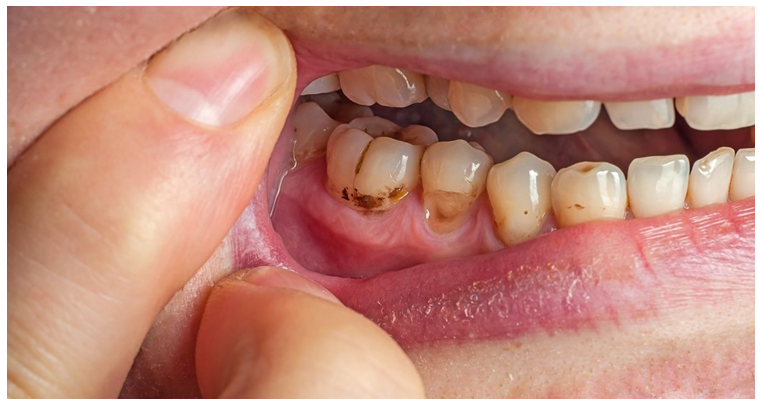

Periodontal Pocket Formation

When the ligament and bone around the teeth are destroyed, deep pockets form between the teeth and gums. These pockets trap bacteria and make the disease worse (Page & Kornman, 1997).

Tooth Mobility and Migration

As the support for the teeth is lost, teeth can become loose and may even shift out of place (Lindhe et al., 2015).